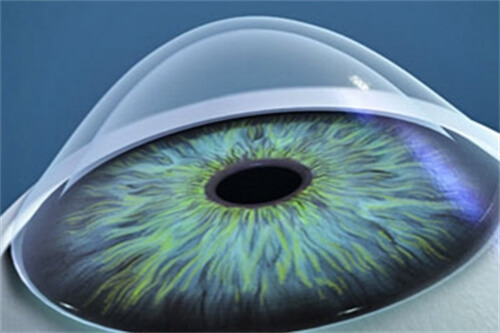

例如,美国爱尔康的PanOptix三焦点晶体,可同时满足远、中、近视力需求,适合需要频繁切换用眼场景的患者;瑞士ICL的胶原共聚物晶体,厚度仅50微米,植入后无异物感,尤其适合角膜偏薄的高度近视人群。